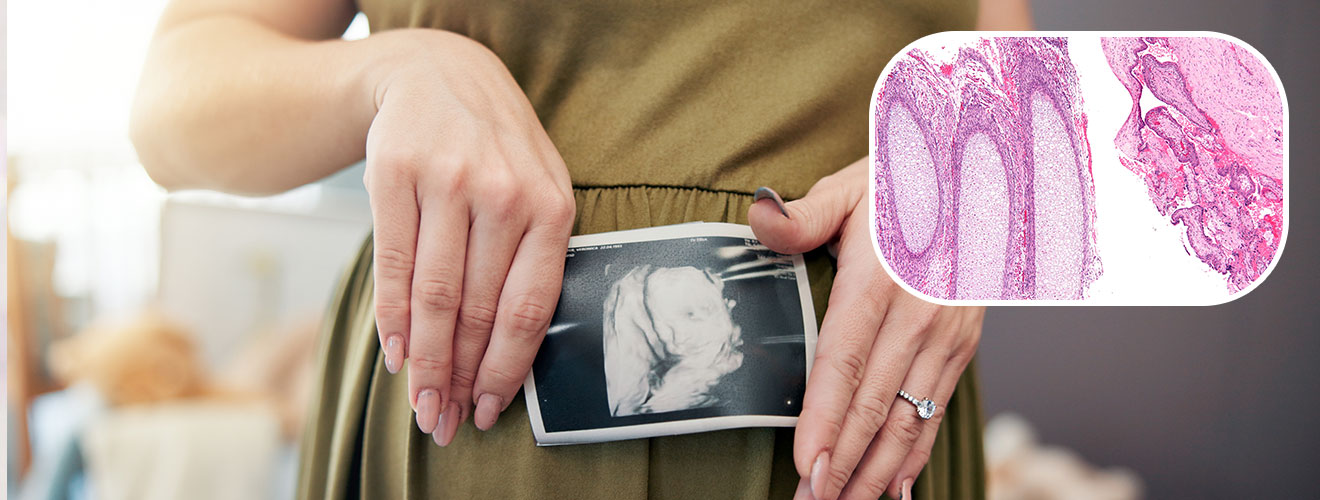

Evacuation of Retained Products of Conception (ERPC) is a minor surgical procedure performed after an incomplete miscarriage. It ensures that the uterus is cleared of any remaining pregnancy tissue to prevent bleeding, infection, and emotional distress.

• Abnormal ultrasound showing remnants in uterus

• A suction or curette is used to remove retained tissue from the uterus